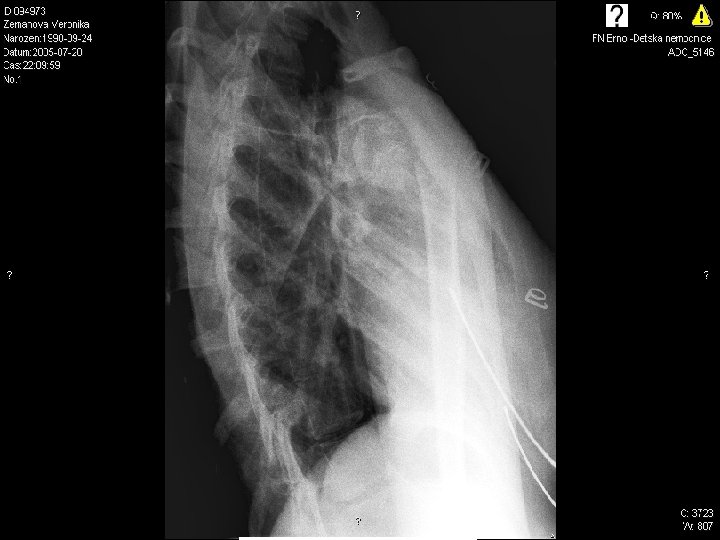

1

2

3

4

5

6

7

8

9

10 17. 4. 2005

Radiodiagnostic test conclusions

10